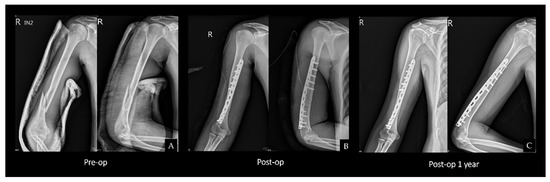

2.2. Surgical Technique

2.4. Single Plating

2.5. Postoperative Protocol